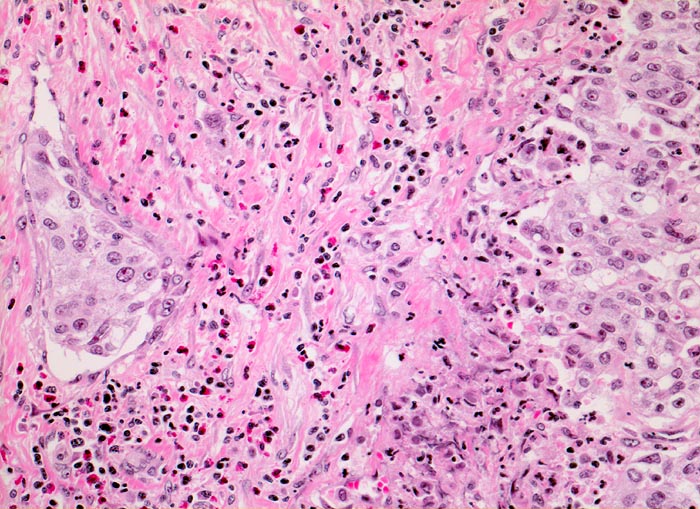

Urothelkarzinom: Gefässinvasion

Ein Gefäss erkennbar an der Endothelauskleidung enthält einen Tumorzapfen. Gemischtes Entzündungsinfiltrat im Stroma mit Beteiligung zahlreicher eosinophiler Granulozyten mit rotem Zytoplasma. Solides Tumorgewebe.

Histologisch lässt sich nicht entscheiden, ob es sich um ein Lymphgefäss oder um ein dünnwandiges Blutgefäss handelt.

Eosinophile Granulozyten finden sich oft bei unspezifischen entzündlichen Prozessen in der Harnblase.